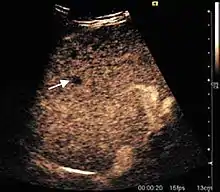

HCC appearance on 2D ultrasound is that of a solid tumor, with imprecise delineation, with heterogeneous structure, uni- or multilocular (encephaloid form). An "infiltrative" type is also described which is difficult to discriminate from liver nodular reconstruction in cirrhosis. Typically HCC invades liver vessels, primarily the portal veins but also the hepatic veins . Doppler examination detects a high speed arterial flow and low impedance index (correlated with described changes in tumor angiogenesis). The spatial distribution of the vessels is irregular, disordered. CEUS examination shows hyperenhancement of the lesion during the arterial phase. During the portal venous phase there is a specific "wash out" of ultrasound contrast agent (UCA) and the tumor appears hypoechoic during the late phase. Poorly differentiated tumors may have a stronger wash out leading to an isoechoic appearance to the liver parenchyma during portal venous phase. This appearance was found in approx. 30% of cases. The described changes have diagnostic value in liver nodules larger than 2 cm.

Ultrasound is useful in HCC detection, stadialization and assessing therapeutic efficacy. In terms of staging related to therapy effectiveness, the Barcelona classification is used which identifies five HCC stages. Curative therapy is indicated in early stages, which include very early stage (single nodule <2 cm), curable by surgical resection (survival 50-70% five years after surgical resection) and early stage (single nodule of 2–5 cm, or up to 3 nodules <3 cm) which can be treated by radiofrequency ablation (RFA) and liver transplantation. Intermediate stage (polinodular, without portal invasion) and advanced stage (N1, M1, with portal invasion) undergo palliative therapies (TACE and sorafenib systemic therapy) and in the end stage only symptomatic therapy applies.